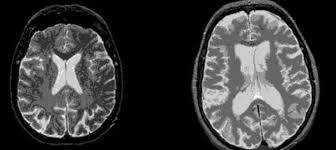

Kalıtsal bir hastalık olan ve kişileri 30’lu ve 40’lı yaşlarda etkilemeye başlayan hastalığın bugüne kadar ancak semptomları hafifletilebiliyordu. Beyin hücrelerini geri dönülmez şekilde yok eden hastalığın gelişimi hiçbir şekilde engellenemiyordu.